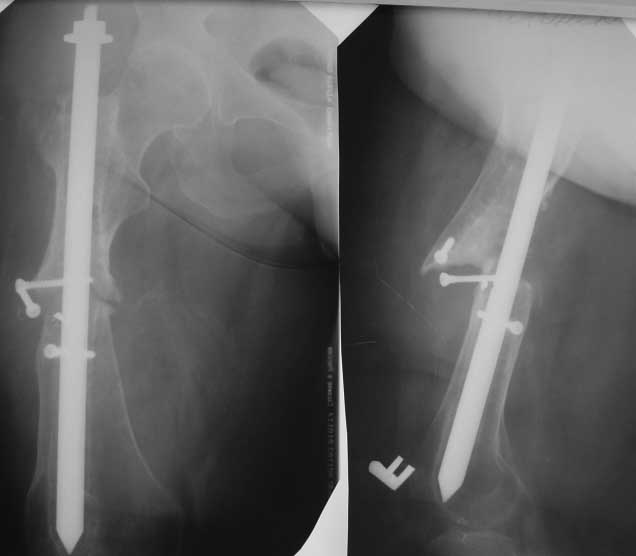

Ложный сустав бедра.

Обратилась пациентка 55 лет. Из анамнеза - травма 6 лет назад, ДТП - переломы С/3 правого бедра, обеих голеней, правого плеча, правой ключицы. Оперирована - остеосинтез голеней аппаратами Илизарова - консолидация, остеосинтез перелома плеча пластиной - формирование ложного сустава, реоперация - удаление пластины, костная аутопластика, аппарат Илизарова - консолидация.

Перелом бедра первично стабилизирован интрамедуллярно 4 -х гранным стержнем типа ЦИТО - формирование ложного сустава. Оперирована повторно 4 года назад- стержнем ЦИТО диаметром 15 мм с попыткой блокировки и компрессии кустарным способом+костная аутопластика костью с гребня подвздошной кости. Обратилась вот с такой Р-гр картиной.

На сегодняшний день абсолютное укорочение 8 см, патологическая подвижность, нога не опорная, контрактуры коленного т\бедренного суставов.